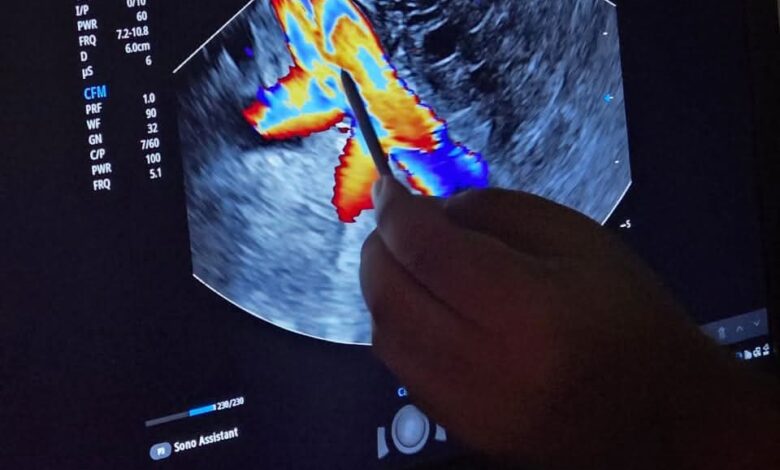

وأوضح بيان الهيئة العامة للرعاية الصحية أنه خلال اليوم العلمي للجهاز الهضمي تم انجاز حزكة من العمليات الناجحة في شق عضلة المريء لعلاج حالات الأكاليزيا، وإزالة حصوات القنوات المرارية وتركيب الدعامات، إضافة إل. استخدام مناظير الموجات الصوتية لأخذ عينات دقيقة من البنكرياس، وهو ما يعكس حجم التطور في خدمات الجهاز الهضمي المقدمة بالمجمع.